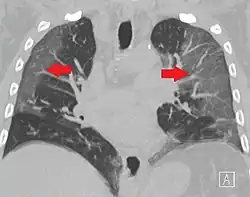

CT image in patient with COVID-19 showing bilateral ground-glass opacities at the periphery of both lungs.

Ground-glass opacity is among the most common imaging findings in patients with confirmed COVID-19.[16][17] One systematic review found that among patients with COVID-19 and abnormal lung findings on CT, greater than 80% had GGOs, with greater than 50% having mixed GGOs and consolidation.[16] GGOs with mixed consolidation has most often been found in elderly populations.[18] Several studies have described a pattern among initial, intermediate, and hospital discharge imaging findings in the disease course of COVID-19. Most commonly, initial CT imaging reveals bilateral GGOs at the periphery of the lungs. During initial stages, this is most often found in the lower lobes, although involvement of the upper lobes and right middle lobe has also been reported early in the disease course.[16][18] This is in contrast to the two similar coronaviruses, SARS and MERS, which more commonly involve only one lung on initial imaging.[19][20] As the COVID-19 infection progresses, GGOs typically become more diffuse and often progress to consolidation.[11][18] This is sometimes accompanied by the development of a crazy paving pattern and interlobular septal thickening.[18] In many cases the most severe pulmonary CT abnormalities occurred within 2 weeks after symptoms began.[17] At this point, many individuals begin showing resolution of consolidation and GGOs as symptoms improve. However, some patients have worsening symptoms and imaging findings, with further increase in septal thickening, GGOs, and consolidation. These patients may develop lung "white-out" with progression to acute respiratory distress syndrome (ARDS) requiring treatment escalation.[17][21]

Preliminary reports have shown many patients have residual GGOs at time of discharge from the hospital. Due to the novelty of COVID-19, large studies investigating the long-term pulmonary CT changes have yet to be completed. However, long-term pulmonary changes have been seen in patients after recovery from SARS and MERS, suggesting the possibility of similar long-term complications in patients who have recovered from acute COVID-19 infection.[22]